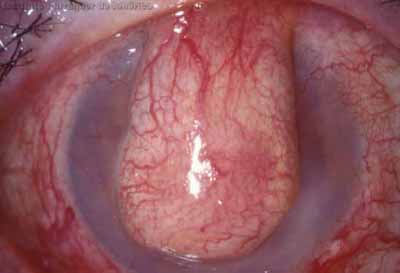

Anillo inmunológico de Wessely

• Es la expresión de la interacción de los antígenos extraños con los anticuerpos que se difunden desde los vasos limbares hacia el estroma.

• Representa la formación de un complejo inmune que activa el sistema del complemento.

• El anillo de Wessely contiene principalmente neutrófilos

• Puede aparecer en procesos no infecciosos

Inicio de síntomas 60 días - 12 meses curación

La vascularización y el hipopion son poco frecuentes en los estadios tempranos de la queratitis. Con el tiempo, en los estados avanzados de invasión estromal, aparecen vasos estromales